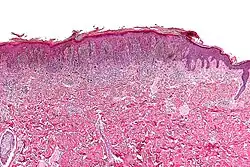

Micrograph of a pigmented spindle cell nevus (top of image). H&E stain.

A pigmented spindle cell nevus is a skin condition characterized by a dark brown to black macule or papule, usually less than 6 mm.[1]